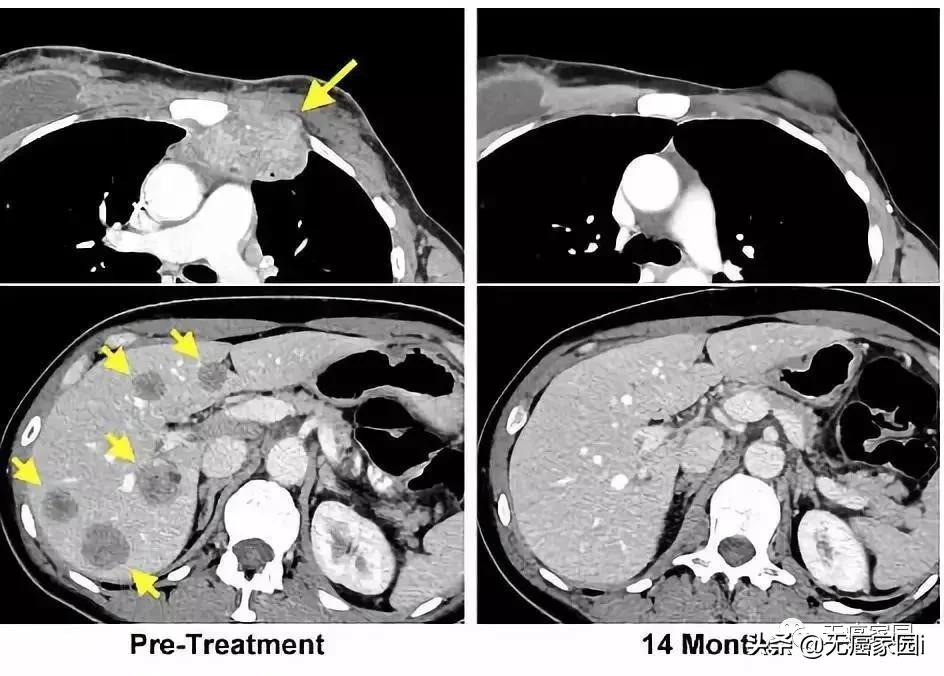

左图黄色箭头是治疗前肿瘤位置;右图是治疗结束14个月后的复查:肿瘤完全消失